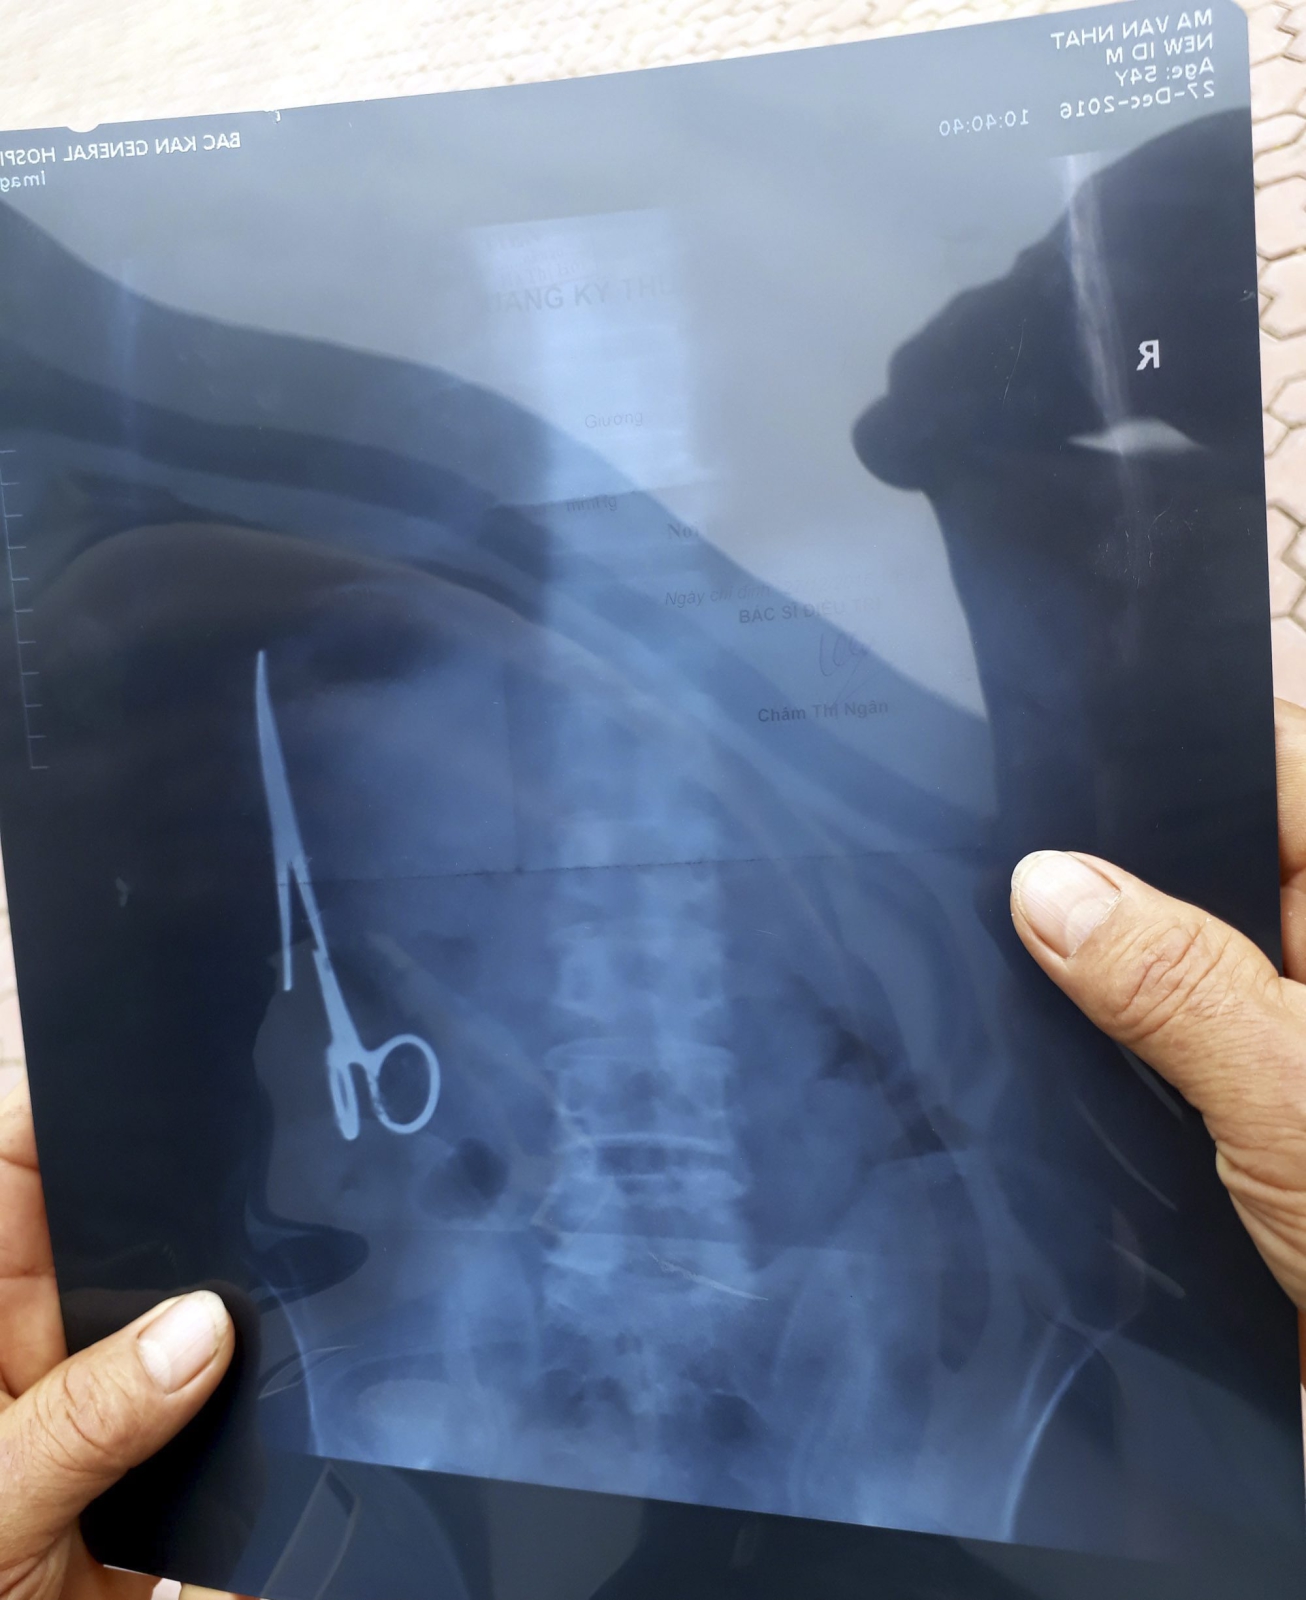

Z żołądka mężczyzny po 18 latach wyjęto nożyczki

Wietnamscy chirurdzy wyjęli z żołądka mężczyzny 15-centymetrowe nożyczki, które miał w brzuchu od czasu operacji przeprowadzonej 18 lat wcześniej. Pacjent przez lata funkcjonował bez problemów.

Mieszkający niedaleko Hanoi mężczyzna w 1998 roku po wypadku drogowym został poddany operacji chirurgicznej, w czasie której omyłkowo zaszyto mu w brzuchu nożyczki. Wykryto je dopiero podczas niedawnego badania ultrasonografem, zleconego ze względu na bóle brzucha, na jakie skarżył się pacjent.

Chirurdzy ze szpitala w Gang Thep Thai Nguyen, ok. 80 km od Hanoi, wyjęli nożyczki w czasie 3-godzinnej operacji. Jak zapewnił w rozmowie z AFP przedstawiciel szpitala, pacjent czuje się dobrze. Cytowany przez lokalne media rzecznik ministerstwa zdrowia powiedział, że mężczyzna przez prawie 20 lat "żył normalnie", mógł bez problemów jeść i pić. Obecnie wietnamskie władze poszukują lekarzy, którzy przeprowadzili niefortunny zabieg w 1998 r.